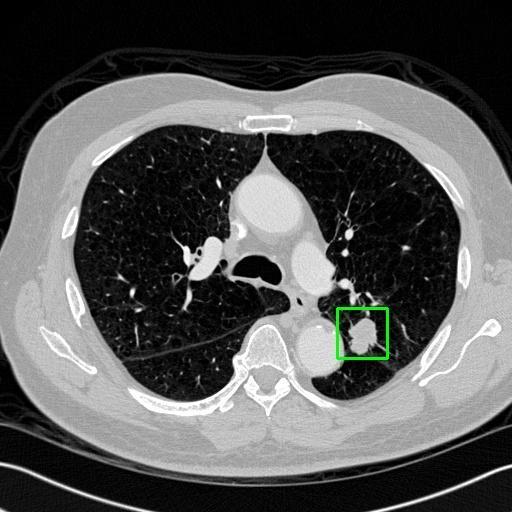

We developed an AI-based system using deep learning models for analyzing lung CT scans to detect and classify pulmonary nodules. We chose the YOLOv11 architecture for its enhanced object detection capability and adapted it specifically for medical imaging, incorporating pixel-level precision and severity classification.

Classification into three severity levels with colored bounding boxes.

Designed a severity classification system that categorizes nodules into null, moderate, and severe using colored bounding boxes, assisting in rapid clinical decision-making.